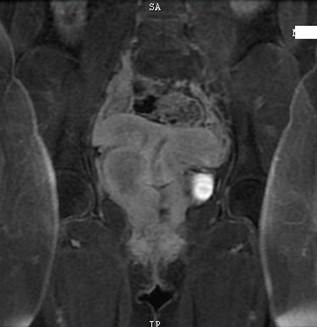

La gammagrafía renal confirmó agenesia renal derecha sin cambios cicatrízales. En la resonancia magnética de pelvis se reportó útero didelfo, vagina septada con oclusión y acumulación de material hemático en espacio lateral derecho (Figura 1). La prueba de embarazo monoclonal fue negativa, el antígeno carcinoembrionario-CEA <0,50 ng/ml (normal) y el antígeno de cáncer ovárico CA 125 en 20,8 U/ml (normal). Por los hallazgos de masa en útero, fue llevada a laparoscopia diagnóstica confirmando los hallazgos imagenológicos. Actualmente en proceso de autorización para septoplastia de vagina. Por el momento sin nuevos episodios de infección urinaria, pero con persistencia de hemorragia uterina anormal.

Figura 1. Resonancia magnética de pelvis en T2 coronal. Se observa útero didelfo y tabique vaginal con oclusión del lumen derecho por presencia de sangre